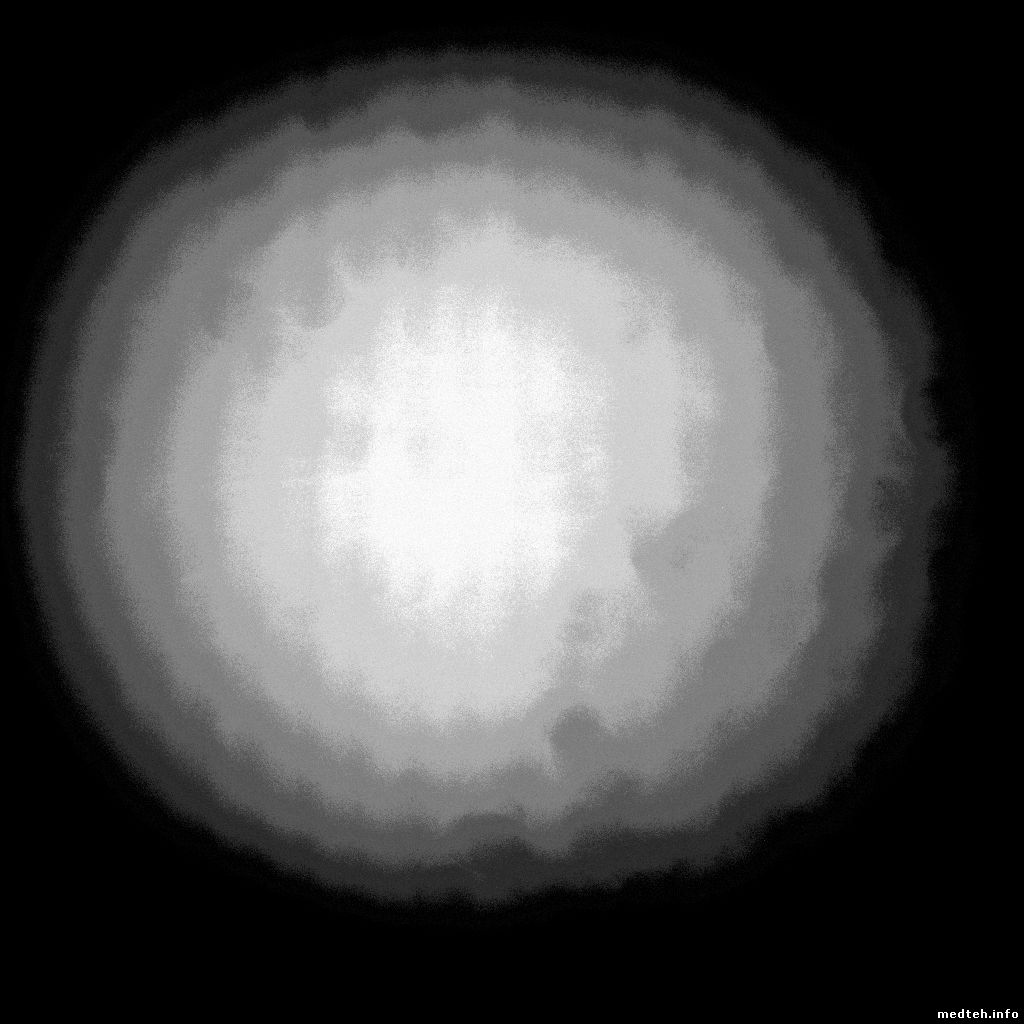

Здравствуйте форумчане!!! Возникла проблема в снимках (файлы прикреплен). Аппарат - КРЦ01 Пони альфа, питающее высокочастотное, управление с пульта. Ситуация в вкратце: демонтировали а потом смонтировали аппарат (другая фирма), что делали не знаю, но аппарат сделал 150 снимков и все (при этом высокое все проходит на ура). Поменяли плату с ПЗС матрицей - снимки пошли но некачественные... круги какие то, причем увеличиваешь режим до 90 кв 10 мас их становиться меньше (3 снимок). Если есть калибровка, то как её проводить или это в другое совсем...прошу помощи. Также прикрепил снимок без объекта

0021619.jpg (88.9 Kb) · 1862006.jpg (104.9 Kb) · 7353036.jpg (77.9 Kb)